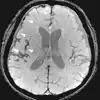

T1 and T2

Each tissue returns to its equilibrium state after excitation by the independent relaxation processes of T1 (spin-lattice; that is, magnetization in the same direction as the static magnetic field) and T2 (spin-spin; transverse to the static magnetic field). To create a T1-weighted image, magnetization is allowed to recover before measuring the MR signal by changing the repetition time (TR). This image weighting is useful for assessing the cerebral cortex, identifying fatty tissue, characterizing focal liver lesions, and in general, obtaining morphological information, as well as for post-contrast imaging. To create a T2-weighted image, magnetization is allowed to decay before measuring the MR signal by changing the echo time (TE). This image weighting is useful for detecting edema and inflammation, revealing white matter lesions, and assessing zonal anatomy in the prostate and uterus.

The standard display of MR images is to represent fluid characteristics in black-and-white images, where different tissues turn out as follows: